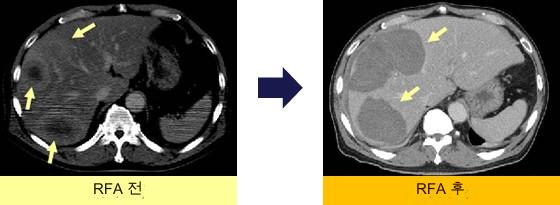

전이성 간암에 대한 RFA

체골동암의 간 전이.표준 치료 없이 최대 지름 13cm, 종양 수 6개의 간 전이에 대해 RFA 시행.

모든 결절을 RFA 후 아주반트로 간동주요법(new FP변법)을 도입했다.